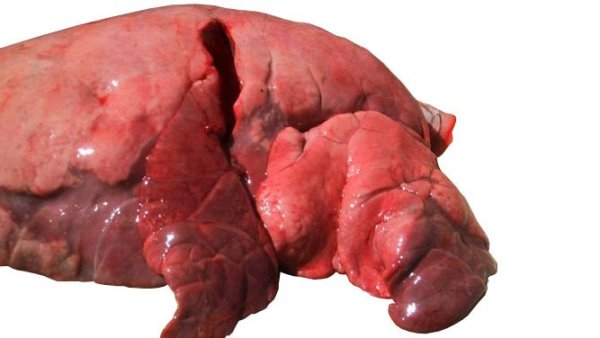

In diesem zweiten Teil behandeln wir das Herauslösen von Zunge, Luftröhre, Lunge und Herz in einem Stück. Wir entnehmen die Organe der Bauchhöhle, sowohl den Verdauungs- als auch den Harn- und Genitaltrakt. Im Kopf legen wir die Nasenmuscheln, das Großhirn und das Kleinhirn frei.

Im vierten Kapitel des Handbuchs befassen wir uns mit der Untersuchung der Organe der Brusthöhle.